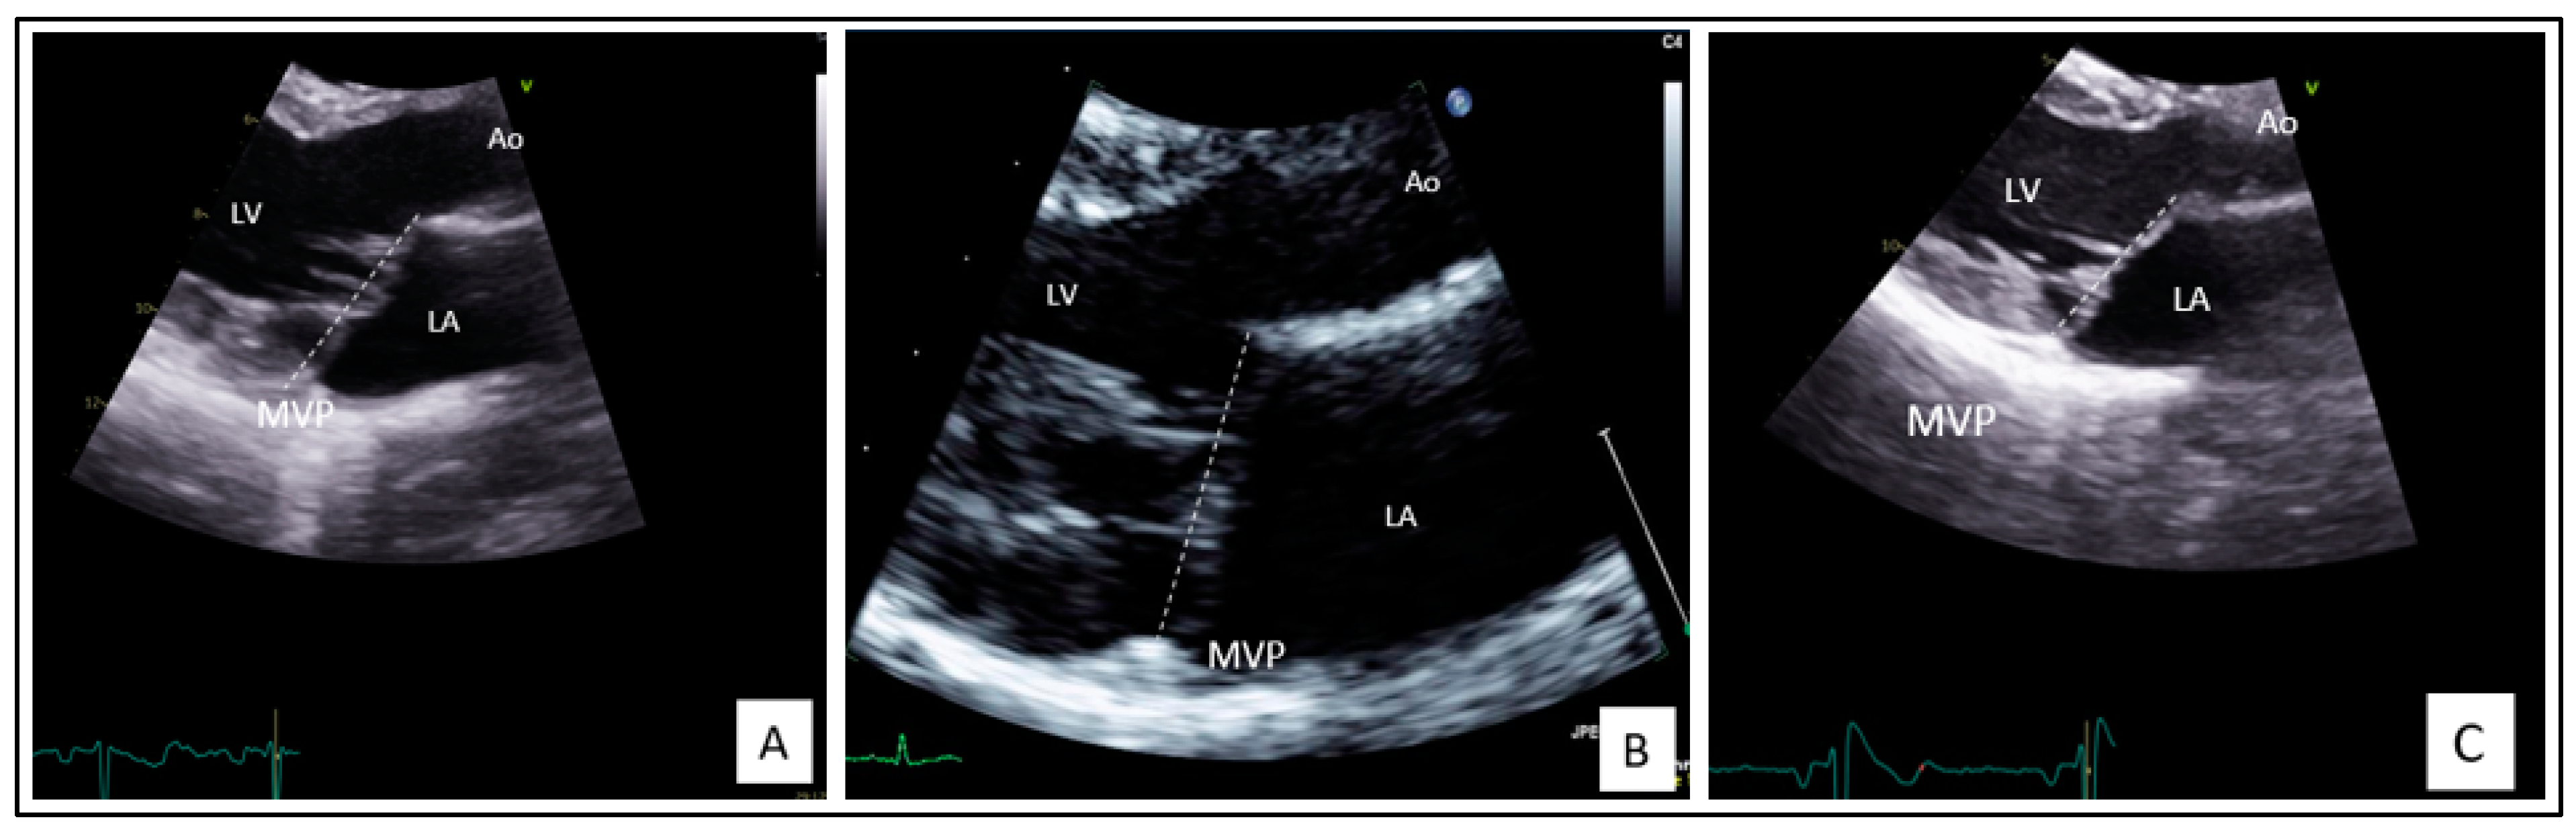

Her echocardiography follow-up showed a constant moderate MR, with mild myxomatous thickened leaflets, the presence of a posterior annulus disjunction, and a typical atrialization of posterior leaflet insertion and posterior systolic curling of the inferolateral wall of the left ventricular (LV) (Figure 2A). The left ventricular ejection fraction (LVEF) remains normal but the LV and left atrium (LA) are mildly dilated according to the European Society of Cardiology Guidelines [20,21].

Figure 2.

Echocardiography of the index case (A), the affected daughter (II-2) (B), and the oldest daughter with a prodromal MVP (II-1) (C). LV: left ventricle; LA: left atrium; Ao: aorta; MVP: mitral valve prolapse.

Family screening revealed one symptomatic daughter (Subject II-2) with a history of two syncopes at 11 years old while she was on a thrill ride and palpitations during an intense run. Her 12 leads ECG at rest, the ECG 24 h Holter, and the exercise stress test were normal. However, her echocardiography showed a bileaflet MVP which predominates on the anterior leaflet with mild myxomatous thickened leaflets, posterior annulus disjunction, and winding movement (Figure 2B). The MVP is complicated by a moderate MR. LVEF and LA volumes were normal. LV was mildly dilated. She received an implantable loop recorder for VA screening.

The oldest sister, 23 years old (Subject II-1), is currently asymptomatic. Her echocardiography revealed a prodromal MVP with a mild holosystolic MR, a posterior annulus disjunction, and a winding movement (Figure 2C). She had no cardiac remodeling and no systolic dysfunction.